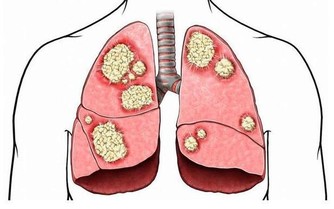

生活中有一些人,身體過於肥胖,就會造成屁股大而自慚形穢,其實在身體和體重健康範圍內,臀部大的人比屁股小的人更長壽,也更健康。根據一項新研究發現,屁股大的人血脂會更好一些。專業人士認為,我們身上的脂肪有“好脂肪”和“壞脂肪”之分。比如屁股上的脂肪就屬於好脂肪,肚子上的脂肪就屬於壞脂肪。好脂肪有助於防止血管硬化,降低糖尿病,甚至還可以清除危害身體器官的炎性脂肪。